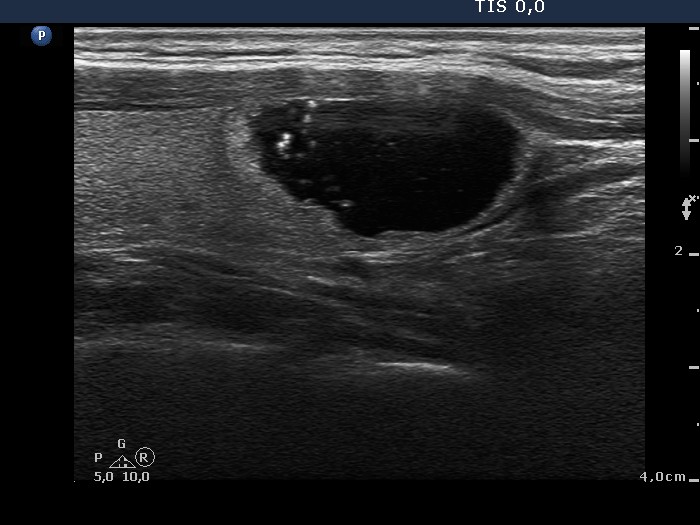

Benign nodular hyperplasia - Case 46. |

Ultrasonography: There was a solitary, cystic-echonormal nodule in the right lobe.

Comment. Most if not all mixed nodules evolve from a solid nodule. The solid part of a mixed nodule appears as a proliferation in most cases.